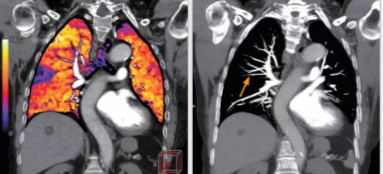

相比傳統(tǒng)成像方式,肺部柔性減影技術(shù)通過人工智能,對(duì)平掃數(shù)據(jù)和CT肺動(dòng)脈血管掃描數(shù)據(jù)進(jìn)行智能比對(duì),解碼并識(shí)別各個(gè)器官(肺、氣管、肺動(dòng)脈、肺靜脈、主動(dòng)脈等)的空間位置,并在三維空間中進(jìn)行體素級(jí)的柔性配準(zhǔn),從而極大提升了不同序列數(shù)據(jù)的空間位置的一致性。通過肺部柔性減影技術(shù)可得到肺強(qiáng)化碘圖,可以顯示出傳統(tǒng)CTPA圖像看不到的小栓塞病變,提高了栓塞檢出率,其結(jié)果甚至可與SPECT吻合。

肺智能柔性減影成像功能發(fā)現(xiàn)亞段肺栓塞